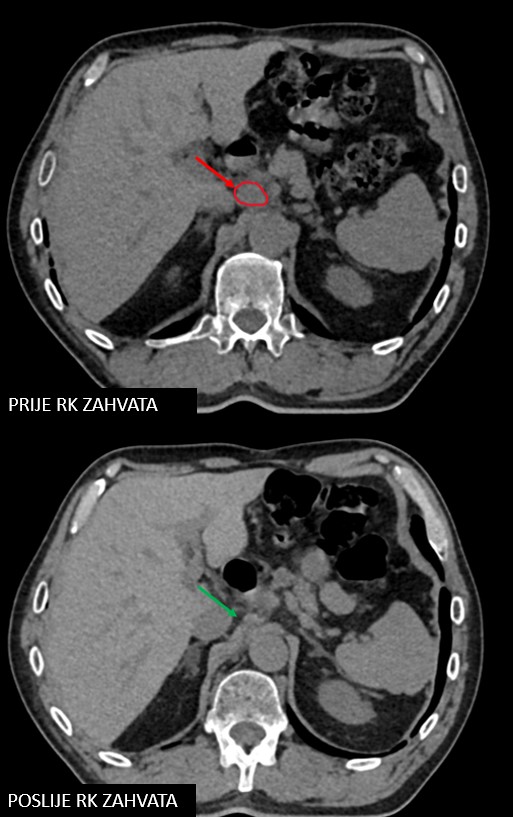

SBRT lymphonodi intraabdominalis (22.11. - 26.11.2021.)

Rezultat – 19 mjeseci nakon RK

Potpuni nestanak tretiranog limfnog čvora